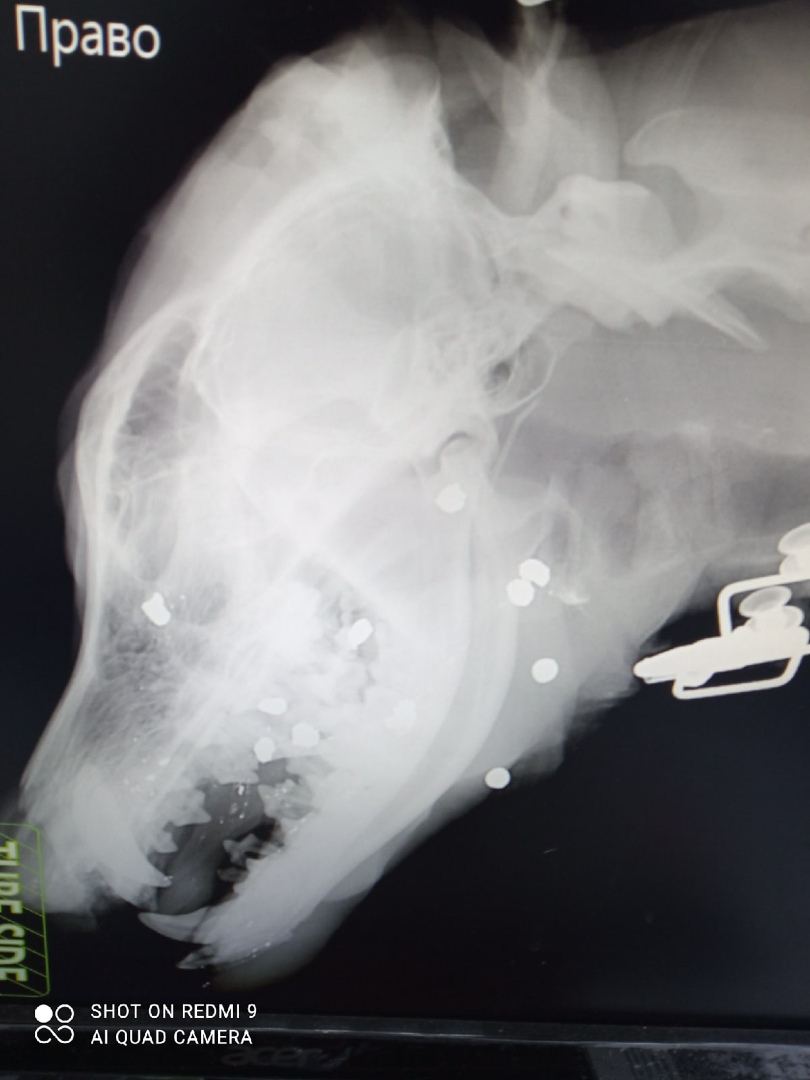

Позже в группе «Приют для собак "Друг" в Сыктывкаре» под записью с просьбой помочь начала появляться новая информация и фотографии. Выяснилось, что собаку расстреляли дробью.

Собаку прооперировали:

— Убрали все вывороченные кости и зубы, так же раздробленные, где-то подзашили, где-то отрезали. Пока не красавец, но все в процессе. Но то, что инвалид на всю жизнь — это факт. Спереди нет ничего, дыра. Ее надо лечить и востанавливать, зубов один или два, вроде, но один под вопросом. Подшили, посмотрим, — сообщает волонтер Ирина Степашина, у которой пес находится на передержке.